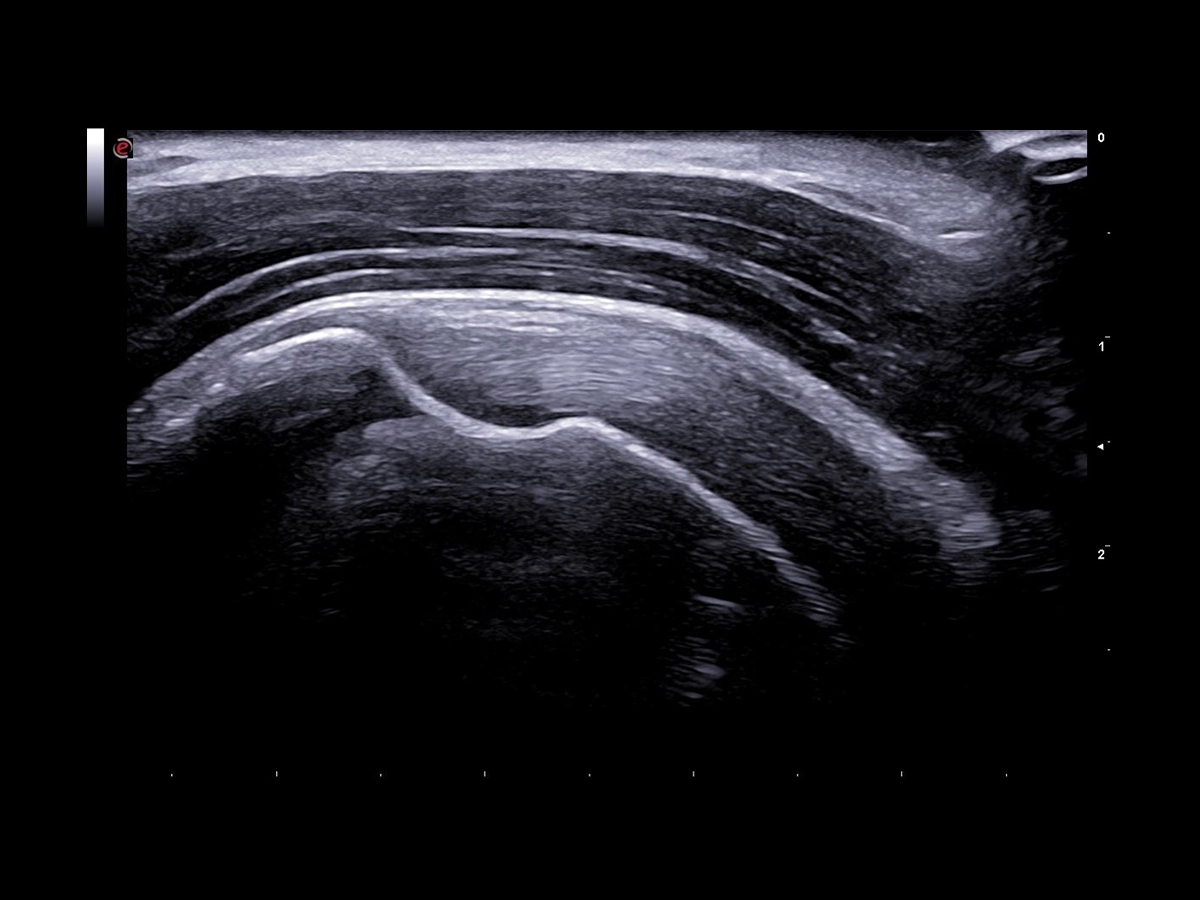

US is most commonly used in the assessment of soft tissue disease or for the detection of fluid collection, and can also be used to visualize other structures, such as cartilage and bone surfaces. Moreover, the real-time capability of US allows dynamic assessment of joints and tendon movements, which can often help to detect structural abnormalities.

Over the past years, huge improvements in image quality have been achieved, such as broadband transducer technology (up to 25 MHz), harmonic and compound imaging, improved focusing, beam steering, and Power Doppler imaging.

Imaging plays a crucial role in musculoskeletal applications. A genuine technological breakthrough in very superficial explorations, the LMX 4-20, Esaote’s brand-new HD Single Crystal probe, which is operating up to 25 MHz, offers unprecedented clarity even in the smallest details without compromising the deeper areas. Applied to this high-density element per multi-layer matrix structure array, XCrystal Technology enables unparalleled sharp and clear imaging to achieve excellence in superficial ultrasound examinations, and becomes the Esaote gold standard in terms of linear probes.